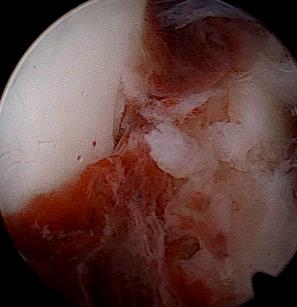

• 关节镜技术联合钉中钉系统全内修复跟骨关节内骨折的临床疗效观察

2026, 32(1):19-25. DOI: 10.12235/E20250392

摘要 (74) HTML (35) PDF 2.90 M (82) 评论 (0) 收藏

摘要:目的 探讨关节镜技术联合钉中钉系统全内修复跟骨关节内骨折的临床疗效。方法 回顾性分析2021年5月-2024年4月该院骨与关节康复科收治,并获得随访的31例闭合性跟骨关节内骨折患者的临床资料。均采取关节镜技术联合钉中钉系统全内修复手术治疗方案。术前及术后均行跟骨侧轴位X线片及足部CT检查,根据影像学结果对骨折类型进行分型,并评价术后骨折复位情况。比较手术前后跟骨高度、宽度、Bohler角和Gissane角。记录术前等待时间、手术时间、术中出血量、住院时间、术后疼痛视觉模拟评分法(VAS)评分等围手术期相关指标及术后并发症发生情况。采用美国足踝外科协会(AOFAS)评分和Maryland足部评分评估临床疗效。结果 术后影像学检查,可见跟骨术后关节面塌陷骨块复位;跟骨高度明显高于术前,跟骨宽度明显窄于术前,Bohler角较术前明显增大,Gissane角较术前明显缩小,差异均有统计学意义(P < 0.05)。术前等待时间为6(4,7)d,手术时间为(188.77±39.53)min,术中出血量为(59.03±23.00)mL,住院时间为(16.49±4.04)d,术后疼痛VAS评分为2(1,2)分,AOFAS评分为92(90,95)分,Maryland评分为92(90,95)分。结论 采用关节镜技术联合钉中钉系统全内修复跟骨骨折,具有可早期开展手术、创伤小、直视下复位、固定可靠和无切口相关并发症等优点,适用于Sanders Ⅱ型和Ⅲ型跟骨骨折。值得应用于临床。